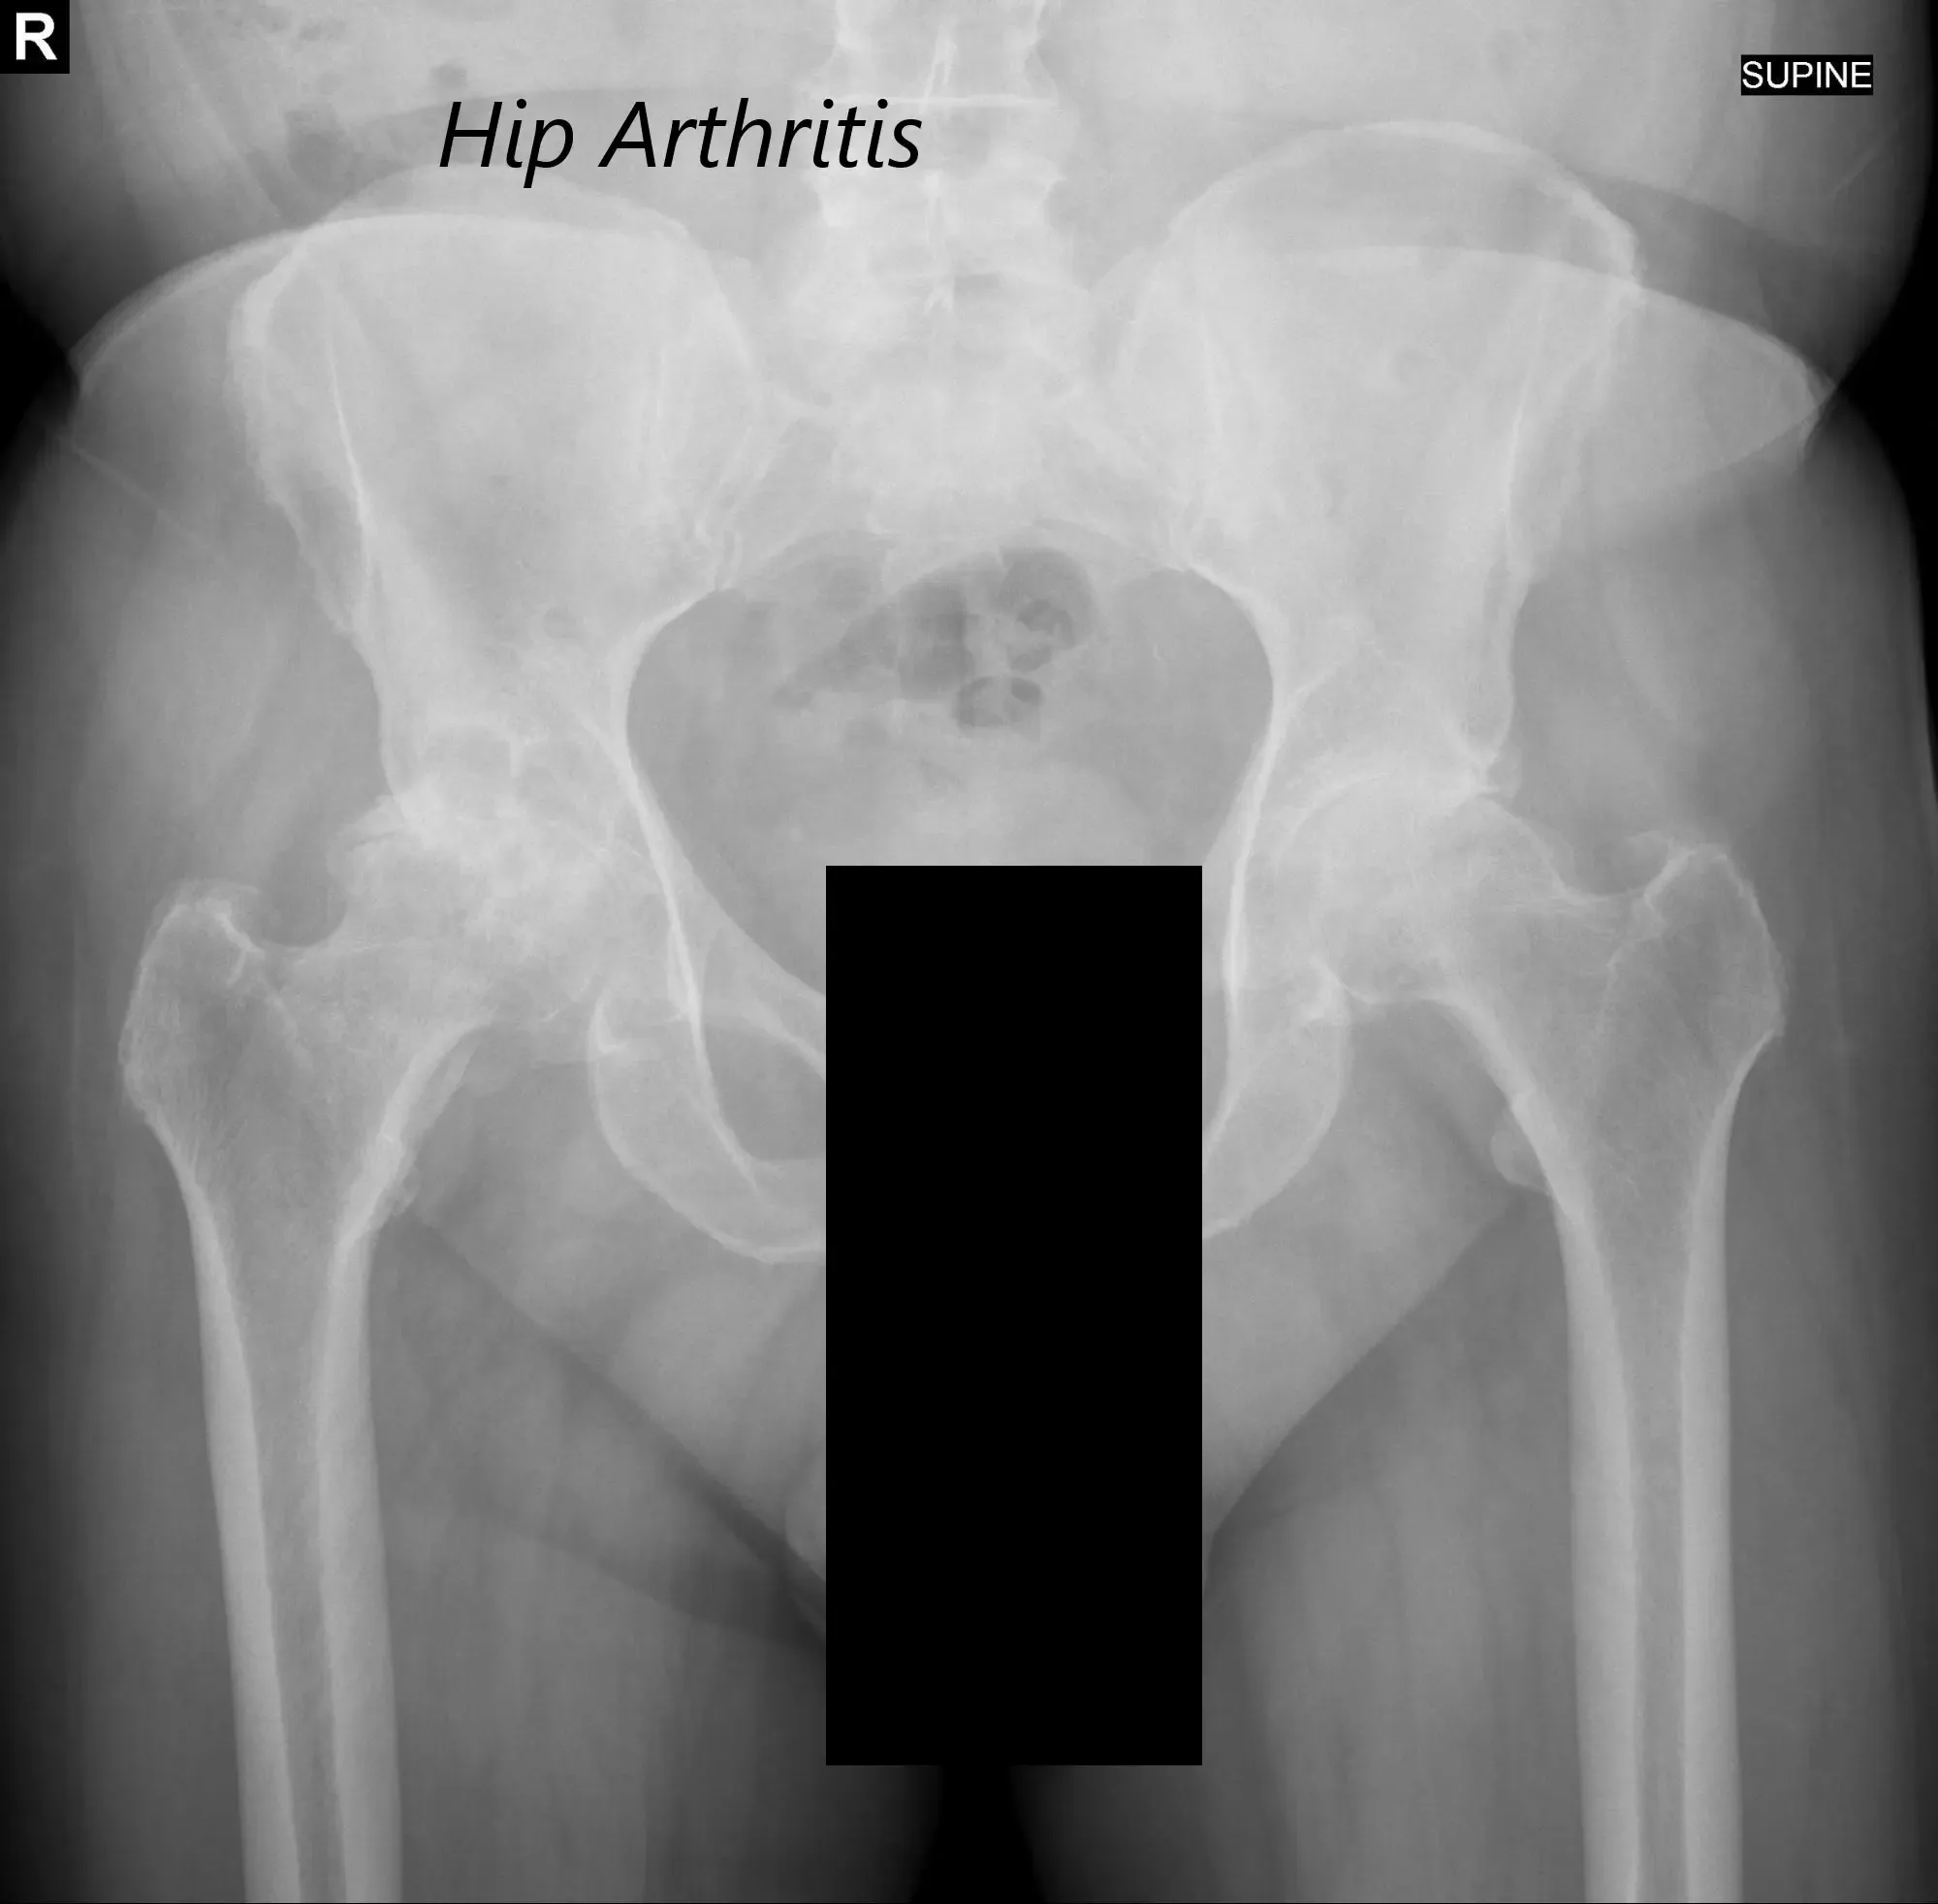

There was bilateral anterior Hip joint line tenderness. The bilateral digital Bryant triangle was comparable suggesting no suprapelvic shortening or lengthening. Imaging studies revealed severe bilateral hip arthritis.

AP view of the Pelvis X ray showing both hip joints with frog leg lateral views of the right and left hip joints suggesting severe bilateral osteoarthritis of the hip joints.